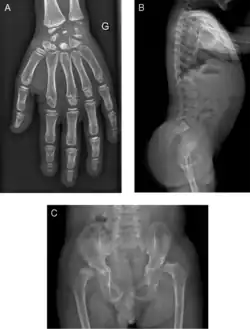

| Radiograph of a WRS child presenting with dysplastic bone growth in various regions of the body. | |